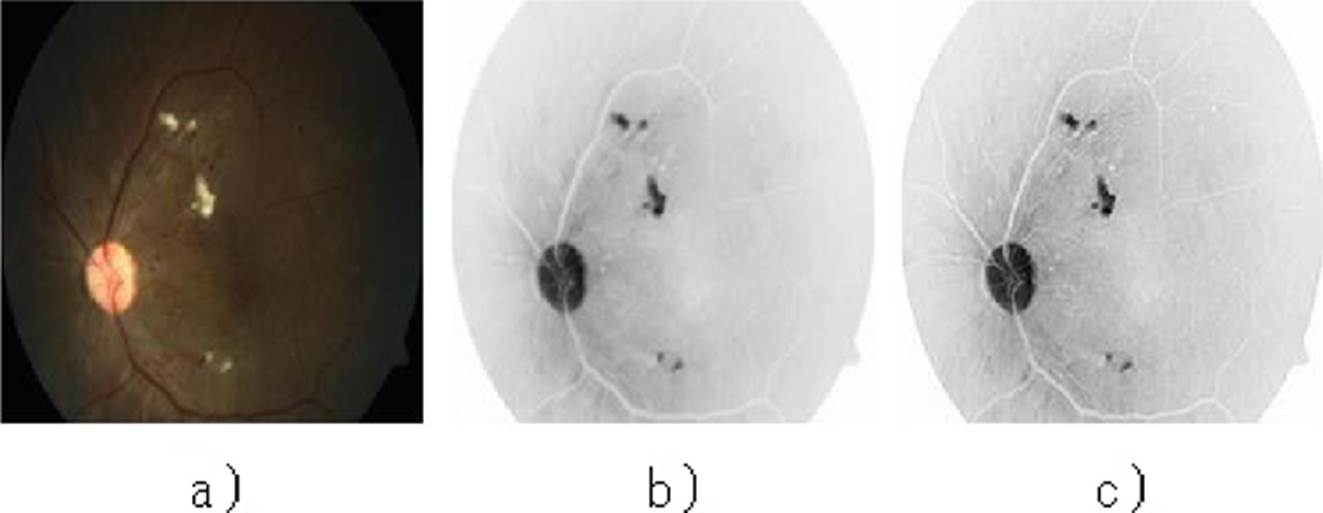

The lesions that occur with DR vary in size and color; this is a relevant feature that allows classifying one from the other. The present work covers the most common types of lesions that allow early detection of DR: Exudates and Microaneurysms. See Figure 2.

Hard and soft exudates were uniformly detected, looking for the particularity of being shiny objects and thus facilitating their detection. In Figure 7 are shown examples of original retinographies, detection of exudates in binary image and the superposition of the images as a sample of the results obtained.